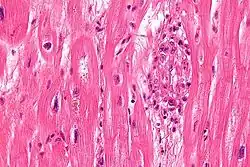

S. pyogenes has a cell wall composed of branched polymers which sometimes contain M protein, a virulence factor that is highly antigenic. The antibodies which the immune system generates against the M protein may cross-react with heart muscle cell protein myosin,[15] heart muscle glycogen and smooth muscle cells of arteries, inducing cytokine release and tissue destruction. However, the only proven cross-reaction is with perivascular connective tissue. This inflammation occurs through direct attachment of complement and Fc receptor-mediated recruitment of neutrophils and macrophages. Characteristic Aschoff bodies, composed of swollen eosinophilic collagen surrounded by lymphocytes and macrophages, can be seen on light microscopy. The larger macrophages may become Anitschkow cells or Aschoff giant cells. Rheumatic valvular lesions may also involve a cell-mediated immunity reaction as these lesions predominantly contain T-helper cells and macrophages.[16]